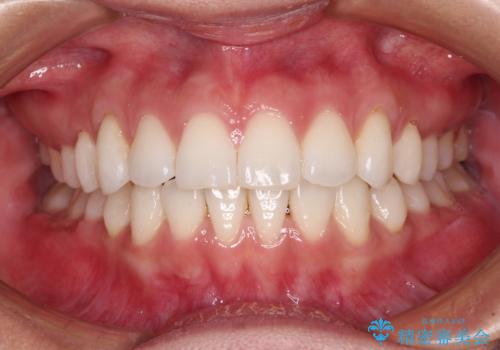

【モニター】インビザラインで口を閉じやすく

- 前に出ている上顎前歯が気になるとのことで来院された患者様です。

インビザラインを用い、IPR(歯と歯の間を削る)と歯列全体を後方に移動させることで、可能な限り前歯の突出感を改善することとしました。

元々の歯列も整っており、横顔の印象の出っ歯ではなかったため、仕上がりに満足できない可能性があると心配しておりましたが、口が閉じやすくなり、患者様には大変満足していただきました。